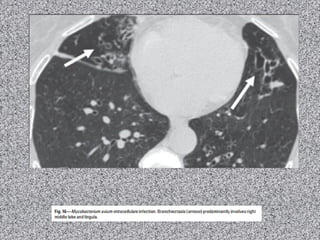

Bronquiectasia focal

Estenose congênita BPE